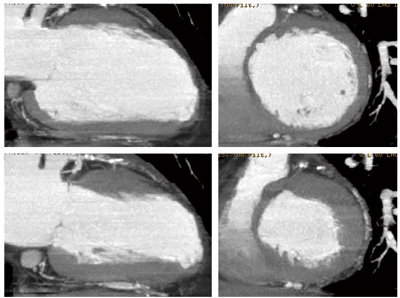

心臓CTを自分で評価し始めたのは今から約5年前,最初はワークステーションでボリュームレンダリングやcurved MPR像を自分で作っていました。その後には,より冠動脈造影様のアンギオグラフィックビューという画像も作成可能になりました。確かにある程度の診断はできるし,全体像をつかむことができて,心臓CTの有用性を感じることはできましたが,どうも結果がしっくりこない,納得できない,理解しづらい,という感覚が残りました(図1)。今から考えれば,それまで冠動脈造影や左室造影,心エコーとして得てきた心臓に関する情報と前述の心臓CT情報が違っていたため,直感的に理解できなかったことがその原因であったと思います。

図1 心臓CTで得られるさまざまな画像 この中で最も簡便かつ理解しやすい画像がSlab MIPであった。

この中で最も簡便かつ理解しやすい画像がSlab MIPであった。

図5には左室壁運動および左室壁性状を検討した結果を示します。左に左室長軸・右に左室短軸像を10mmのSlab MIPで示し,上段に拡張期・下段に収縮期像を示すことによって壁運動を示しています。一見してわかるように,前壁心筋梗塞症例で前壁中隔の心筋の菲薄化,壁運動の低下が把握できます。さらに,よく見ると冠動脈も描出されており,左室壁と冠動脈の同時評価ができることがわかります。

図5 左室壁性状・左室壁運動もSlab MIPで容易に評価可能